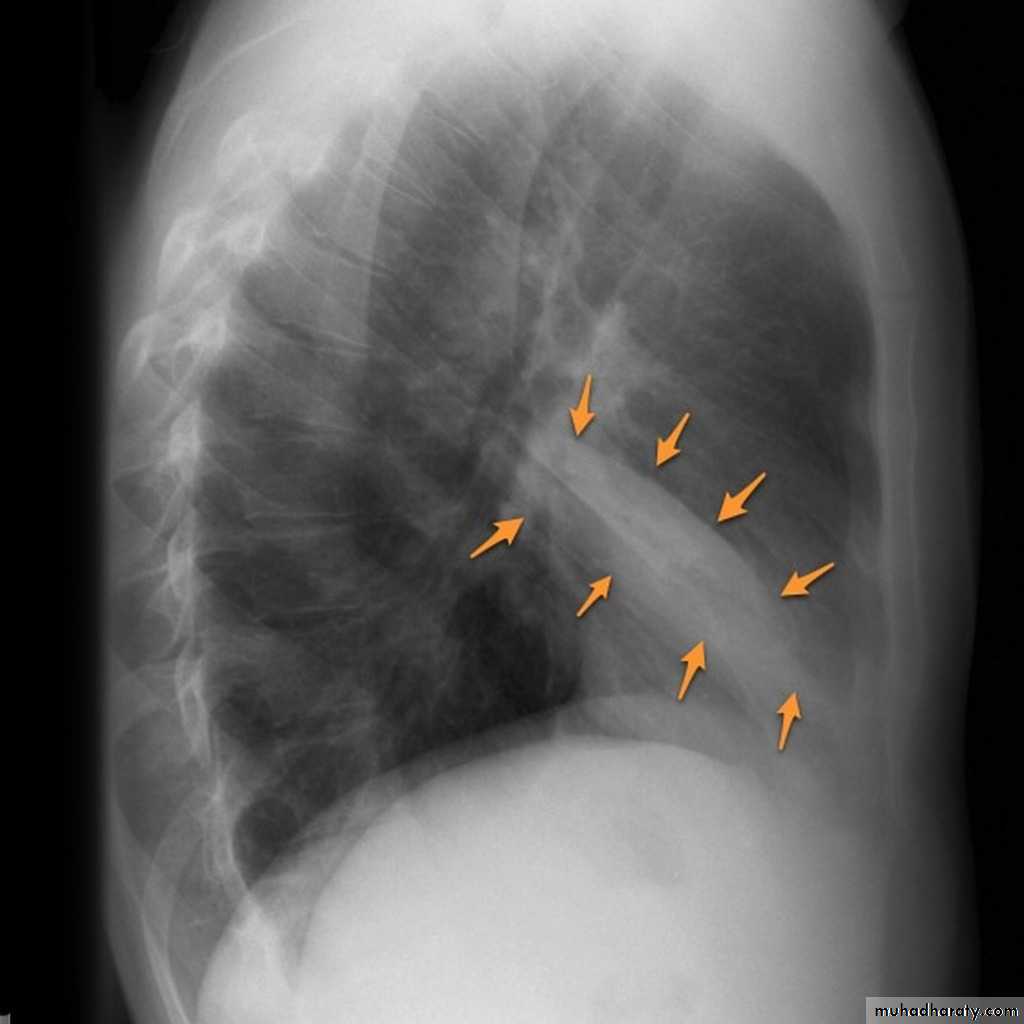

The horizontal fissure (right) is often seen on a normal frontal view

The oblique fissures are often seen on a normal lateral view .

Lobes and fissures

This cut-out of a lateral chest x-ray shows the positions of the lobes of the right lung

On the left the oblique fissure is in a similar position but there is usually no horizontal fissure, and so there are only two lobes on the left.